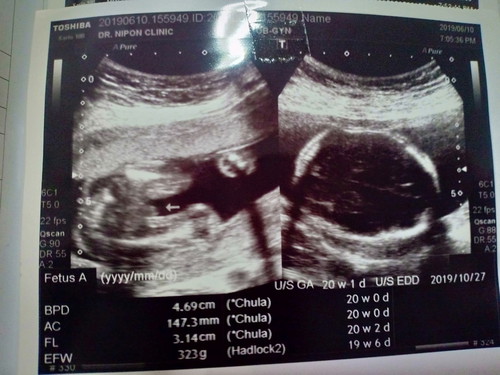

20 w

ตอนแม่ ๆ ตั้งครรภ์ 5 เดือน ไปซาวด์ น้ำหนักน้องเท่าไรกันบ้างคะ

ของเราเป็นช่วง 22 สัปดาห์ค่ะ ประมาณ 520g.

23 สัปดาห์ 630 กรัมค่ะ